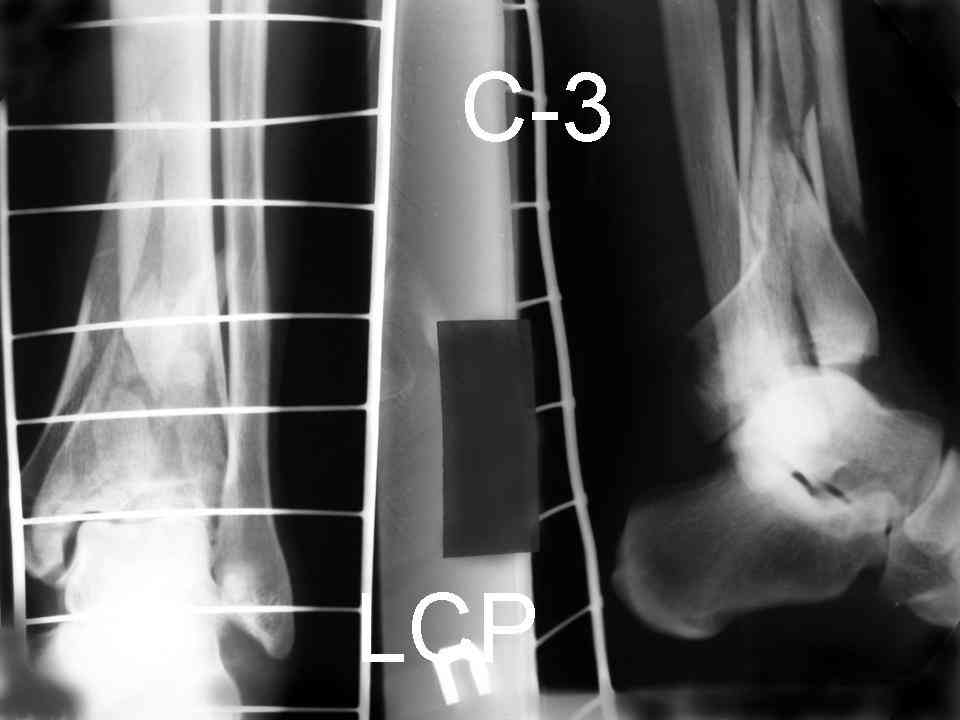

Посылаю результат лечения предыдущего больного через год.

С уважением Дрягин